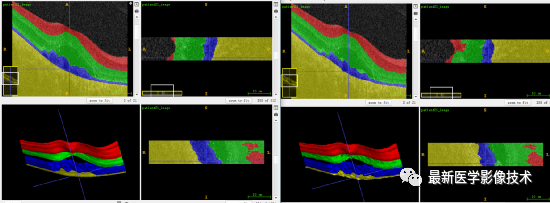

5、验证集分割结果

验证集平均结果